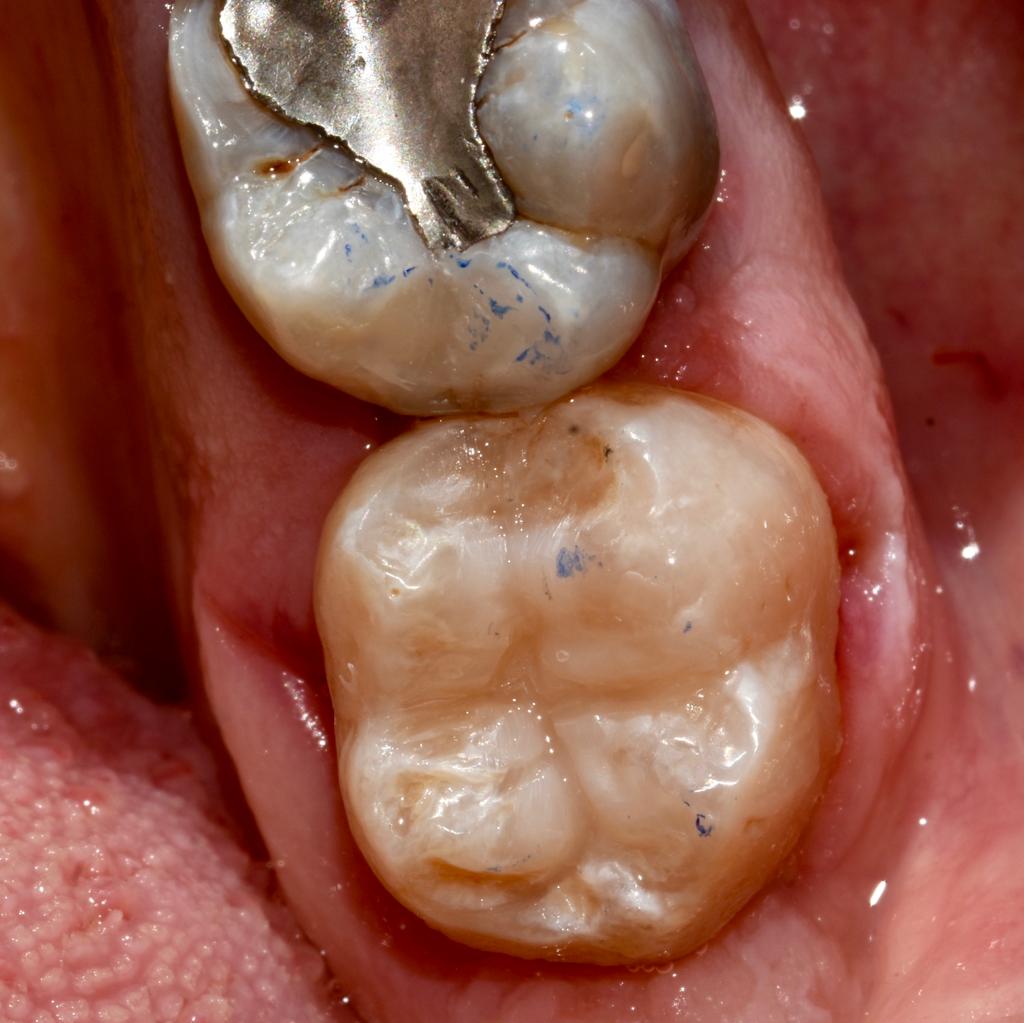

Attraverso l’utilizzo di uno strumentario adeguato, la moderna conservativa si basa sul concetto di minima invasività. Cioè la rimozione esclusiva del tessuto dentario danneggiato dalla carie e la sua sostituzione con materiali da otturazione.

Lo studio Kennedy si avvale di materiali di alta qualità oltre che di specifici protocolli clinici per restituire l’integrità del dente trattato oltre che ad una elevata estetica.

Alcuni casi clinici